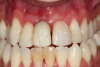

Fig 6. Image of the patient’s mature smile.

Figure 6